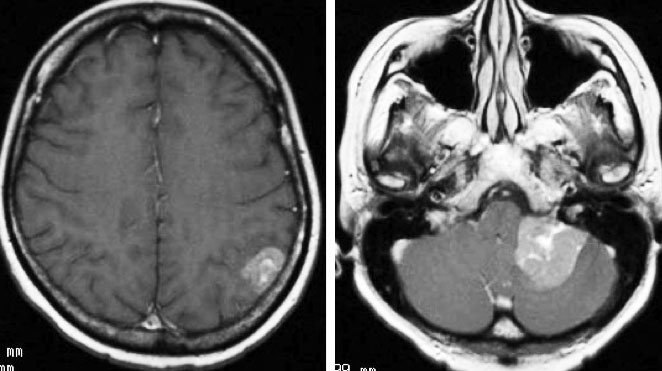

乳癌の多発脳転移の例

全脳照射3ヶ月後のMRIです。左の頭頂葉の転移巣は消失していますし,左の小脳転移は手術摘出できていて再発もありません。このように乳癌は,多発転移であっても比較的に制御しやすいものです。しかし,一度消えた病巣が再発したり,また新たなところに脳転移が生じるという可能性もあります。

肺小細胞癌の転移 multiple metastases of lung small cell cancer

左のMRIは,肺小細胞癌の患者さんに脳転移が無いか確かめるために撮影されたものです。転移はありませんでした。右側のMRIは,そのわずか3週間後に撮影したものです。数十個の脳転移がありました。肺小細胞癌では短期間の間に無数の脳転移を生じることがあります。かつては脳転移を予防するための予防的全脳照射という治療が行われていたくらいです。